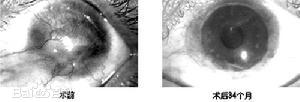

角膜化学性烧伤晚期消除睑球粘连,为争取复明创造条件。

⑵角膜移植:碱烧伤后的角膜移植具有很大危险性,并发症多。伤口愈合不良、移植片感染、排斥反应后移植片自溶、迁延性葡萄膜炎及眼球萎缩等一系列严重的并发症都可能发生。但在烧伤早期,如角膜溃疡有穿孔趋势,可立即作治疗性板层角膜移植。在烧伤后,变薄的角膜伴密集的新生血管或变厚伴有大量增生瘢痕及肉样血管翳,穿透性角膜移植不能成功。